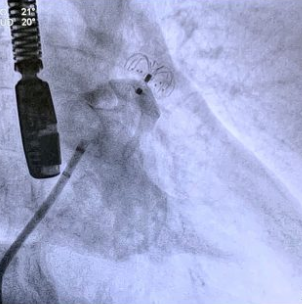

Como é feito o procedimento?

É puncionada uma veia localizada na virilha.

Após a punção, é posicionado um cateter no apêndice atrial esquerdo.

A prótese oclusora do apêndice atrial esquerdo é posicionada, liberada e testada

através do cateter.